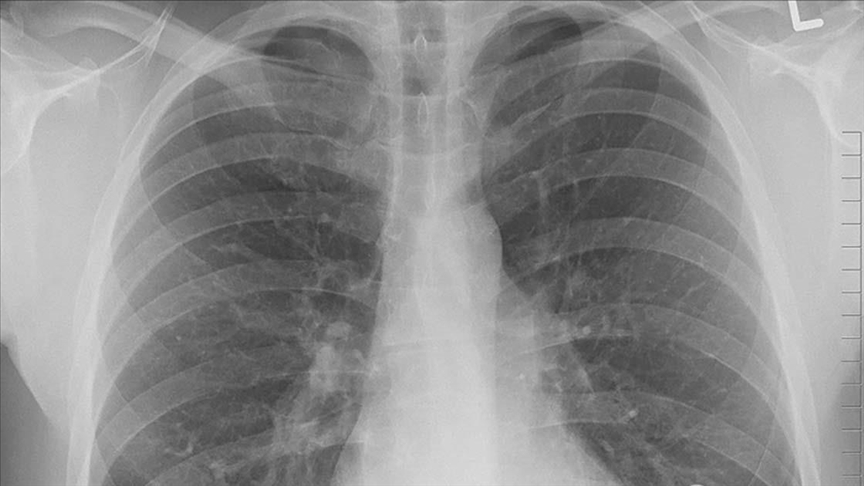

KOAH hastaları akciğer kanseri açısından da risk altında

İstanbul, 21 Kasım 22 (TAK):  Medicana Kadıköy Hastanesi Göğüs Cerrahisi Uzmanı Prof. Dr. Bülent Arman, KOAH hastalarının akciğer kanseri açısından da risk altında olduğunu belirtti.